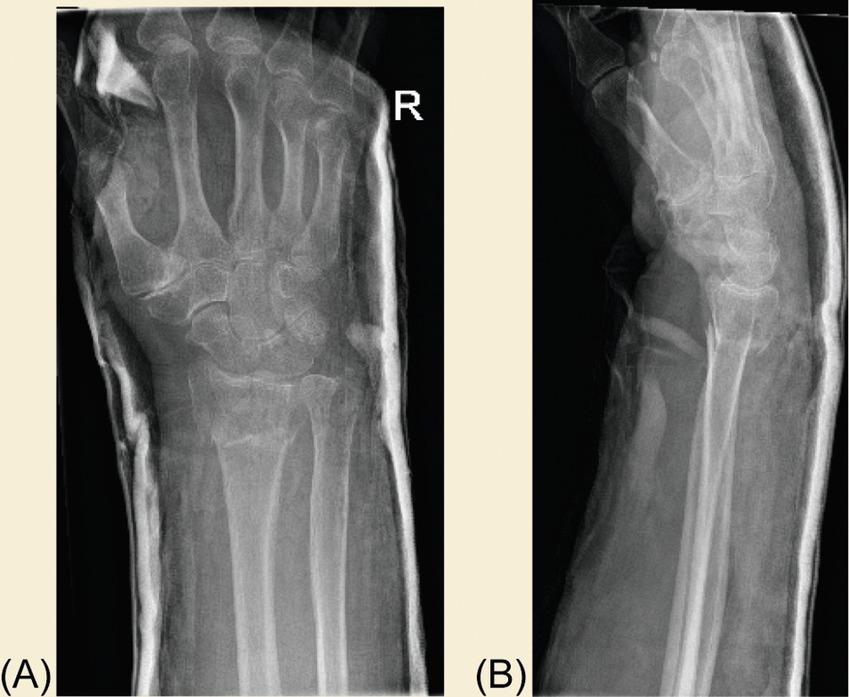

A 65-year-old woman falls on an outstretched hand whilst gardening, sustaining a right distal radius fracture. She is right hand-dominant and works as a shop assistant. Fig. 1 A and B demonstrate her presentation radiographs. Fig. 2 A and B are her satisfactory postreduction radiographs following manipulation under regional anesthesia.

Fig. 1, Radiographs showing a severely displaced distal radius fracture.